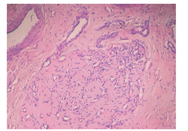

29例NICH:见瘤组织呈小叶状结构,小叶大小不等、形状不一,由大量微血管组成,衬以内皮细胞,细胞核呈"靴钉样"向管腔内突出,小叶中央见星形管腔,间质为致密纤维组织,可见明显的小动脉及小静脉,散在淋巴管结构。其中6例见管腔内充红细胞,但未见血栓形成;5例见管腔内充淋巴液;2例见小灶钙化。3例RICH:见瘤组织呈小叶状结构,小叶间纤维脂肪组织增多,大部分血管闭锁,余血管腔变窄,内皮细胞较扁平,可见小灶性出血坏死、钙化及含铁血黄素沉着。

瘤组织常发生在真皮层和/或皮下组织,呈小叶状结构,小叶大小不等、形状不一,由大量微血管组成,微血管大小不一、形状不规则,腔内衬以内皮细胞。内皮细胞胞质常不明显,核突出,似"靴钉样"(图2)。小叶中央见星形管腔,管壁厚薄不一。间质为致密纤维组织,可见淋巴管及明显的小动静脉。核分裂象少见。可见肥大细胞数量增多[11]。而RICH与NICH相比,同样的小叶状结构内可见多量的血管闭锁、纤维化,余血管腔狭窄(图3),内皮细胞扁平,核不突出,间质见更多的纤维脂肪组织,血栓、含铁血黄素沉着、灶性钙化可见。